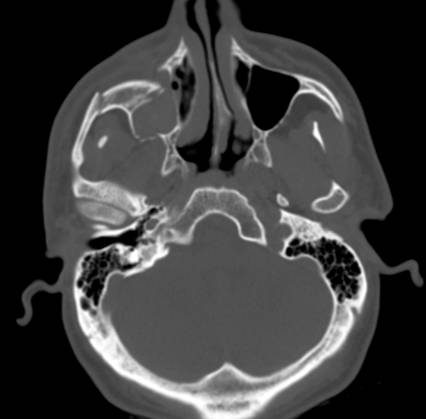

| Battle sign - Think Basilar Skull Fracture | ||||

![]() |

EARS: lacerations, discharge, hearing grossly intact, hemotympanum, Battle’s Sign/mastoid ecchymosis (Base of Skull/Middle Cranial Fx),